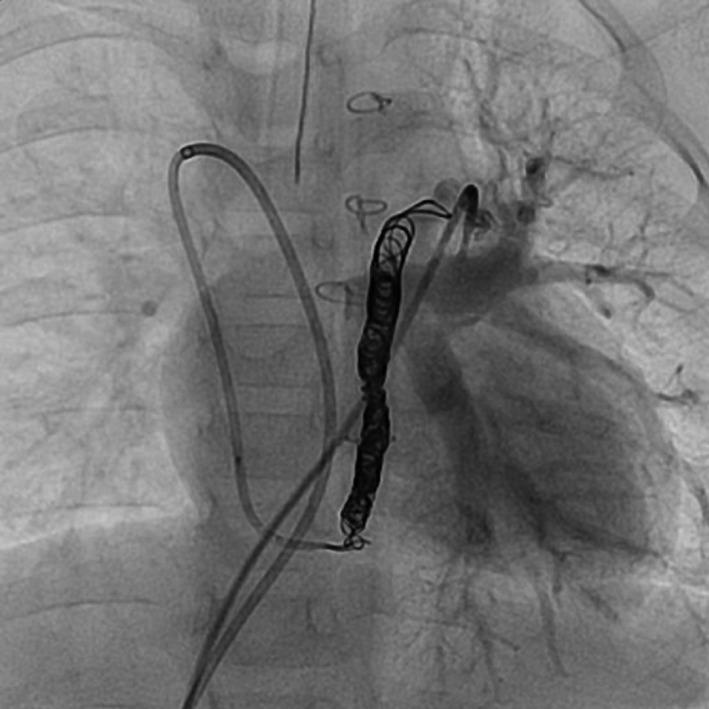

Double drainage of total anomalous pulmonary venous connection revealed after surgical repair of a supracardiac total anomalous pulmonary venous connection.

Mixed type TAPVC with double drainage, where the second vertical vein enlarged rather than atrophied after surgery. If we did not recognize left-to-right shunting before surgery, it can be treated with catheterization as demonstrated by our case.